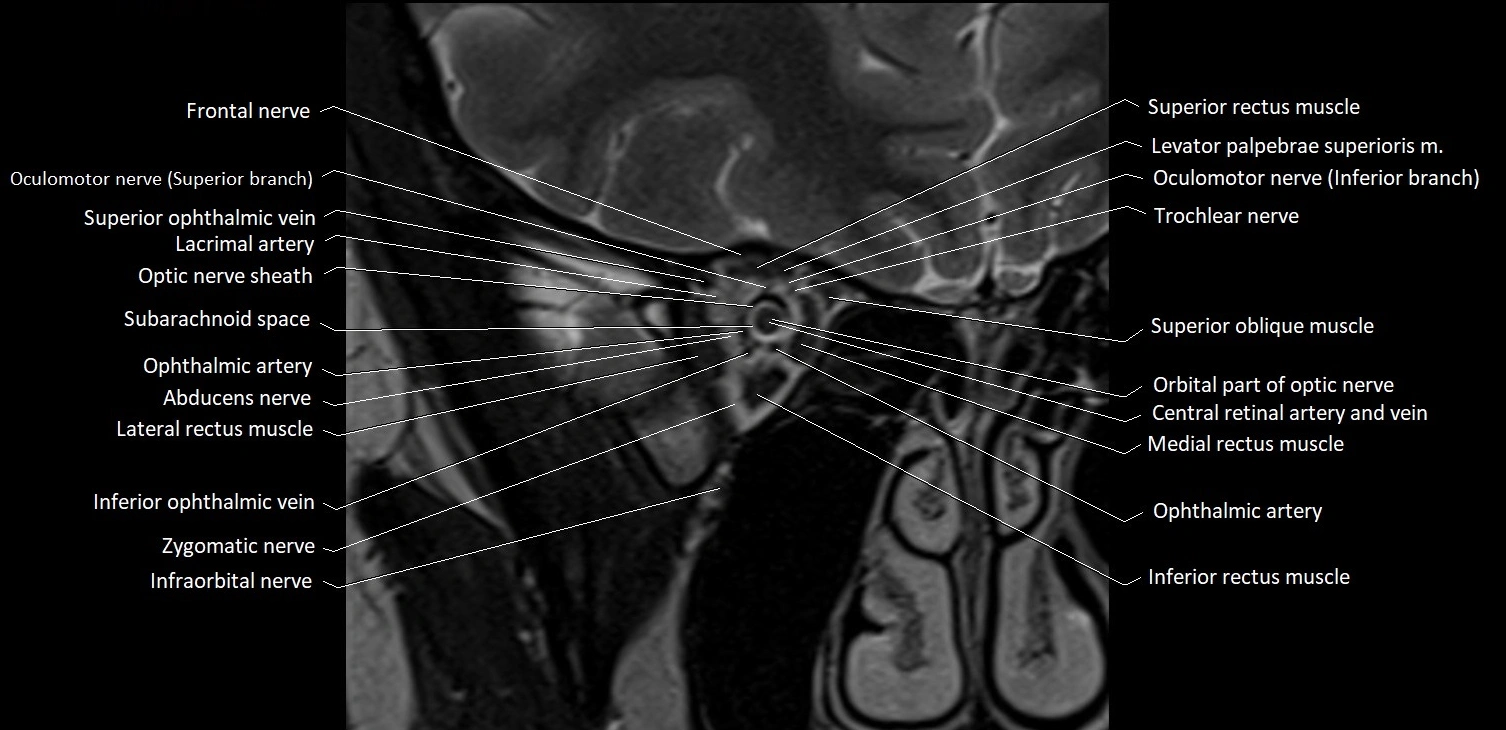

- Abducens nerve (Cranial nerve VI)

- Abducens nerve (orbital part )

- Frontal nerve

- Inferior ophthalmic vein

- Inferior rectus muscle

- Infraorbital nerve

- Lacrimal artery

- Lateral rectus muscle

- Levator palpebrae superioris muscle

- Medial rectus muscle

- Oculomotor nerve (Superior branch)

- Oculomotor nerve (inferior branch)

- Optic Nerve (Cranial Nerve II)

- Optic nerve sheath

- Orbital part of optic nerve

- Subarachnoid space of optic nerve

- Superior oblique muscle

- Superior ophthalmic vein

- Superior rectus muscle

- Trochlear nerve (Cranial nerve IV)

- Zygomatic nerve